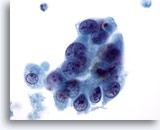

Figure 28: Breast FNA, Ductal carcinoma in situ. This is a cellular aspirate showing clusters of tumor cells, single malignant cells and foamy macrophages. Ductal carcinoma in situ (DCIS) often shows myoepithelial cells overlying the malignant cell clusters. Tumor cells tend to be clustered rather than single as in invasive tumor. In addition, tubular structures are not associated with DCIS. Comedo DCIS is characteristically associated with necrosis and calcium. 40x

Figure 28

Breast FNA, Ductal carcinoma in situ.

This is a cellular aspirate showing clusters of tumor cells, single malignant cells and foamy macrophages. Ductal carcinoma in situ (DCIS) often shows myoepithelial cells overlying the malignant cell clusters. Tumor cells tend to be clustered rather than single as in invasive tumor. In addition, tubular structures are not associated with DCIS. Comedo DCIS is characteristically associated with necrosis and calcium.

40x